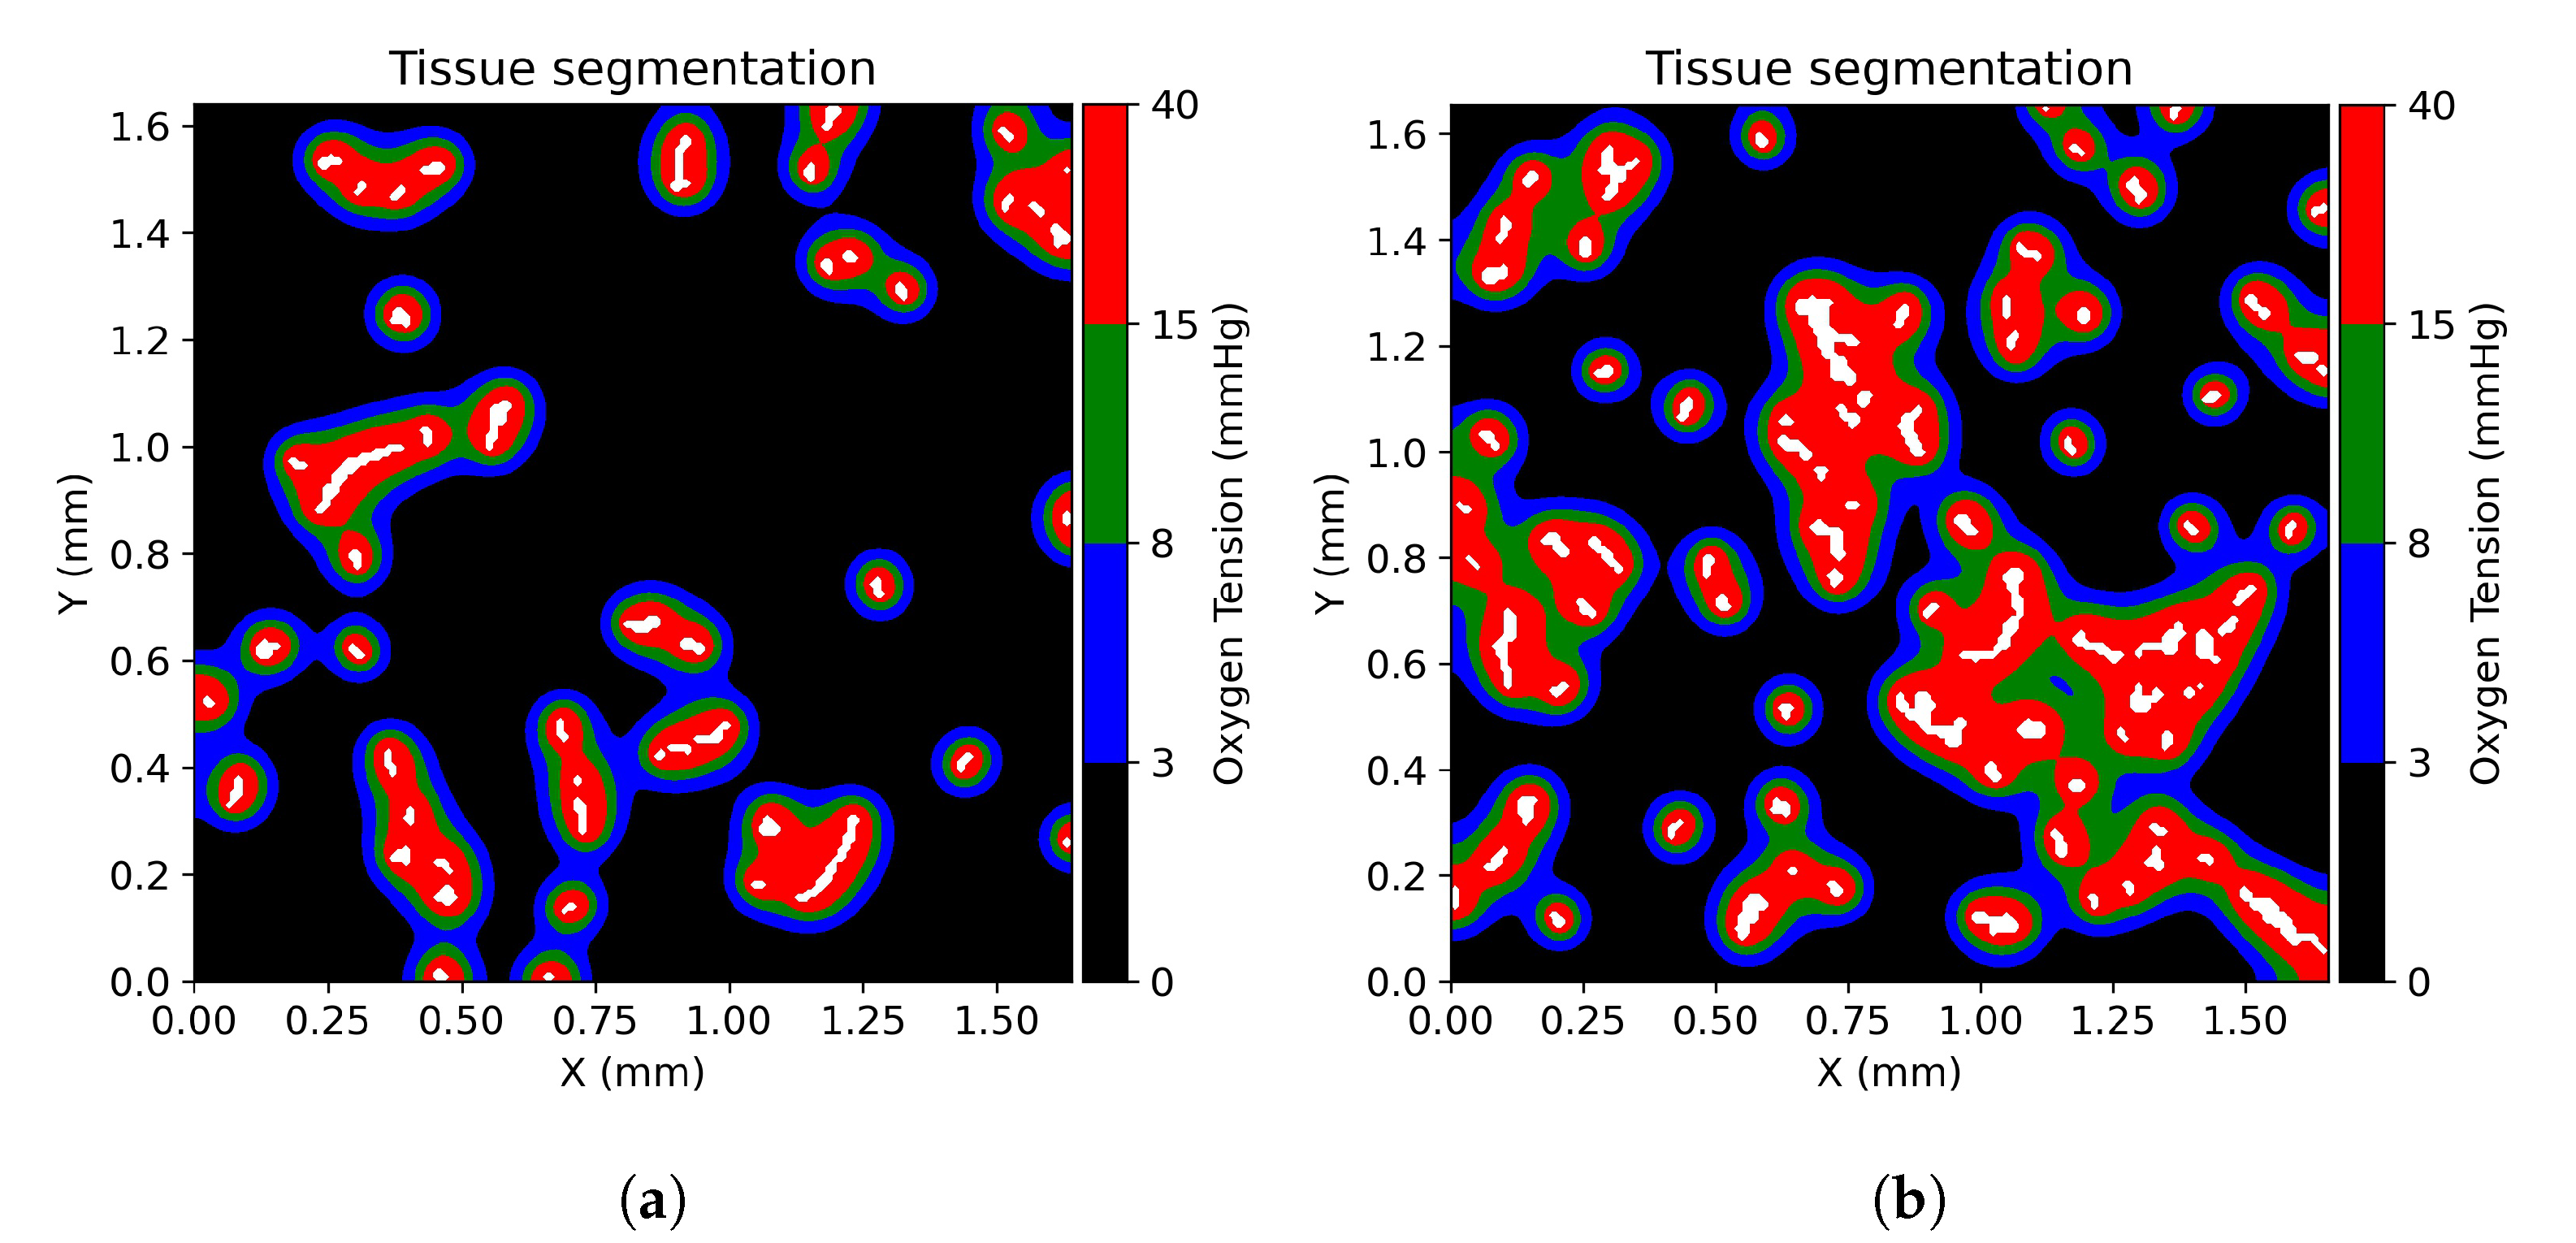

3.1. Tissue Oxygenation and Oxygen Dependent Tissue Segmentation